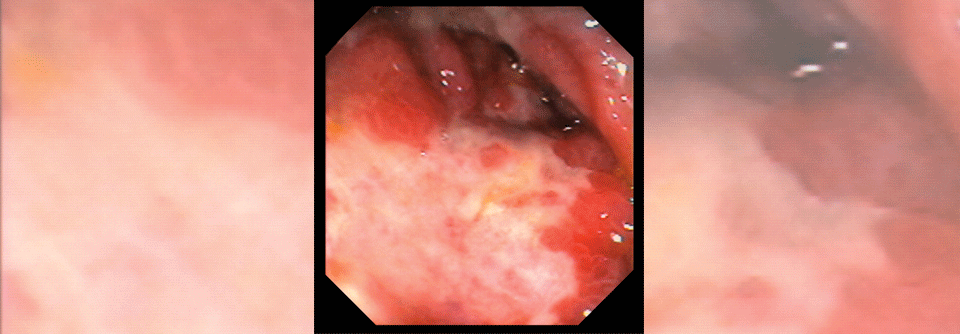

Venöse und arterielle thromboembolische Ereignisse treten bei Krebspatienten vermehrt auf. Die Krebstherapie kann zu diesem erhöhten Risiko beitragen – auch Checkpoint-Inhibitoren, wie zunehmend deutlich wird.

Durch die Möglichkeit der anhaltenden Krankheitskontrolle trotz fortgeschrittener onkologischer Erkrankung nimmt die Bedeutung sekundärer Ursachen für Morbidität und Mortalität immer weiter zu. Dr. Florian Moik, Medizinische Universität Graz, stellte in seiner Promotionsarbeit an der Medizinischen Universität Wien fest, dass Patienten mit einer Krebserkrankung unter CPI-Therapie ein erhöhtes Risiko für venöse thromboembolische Ereignisse (VTE) haben. Und diese stellen offenbar ein ungünstiges prognostisches Zeichen in genannter Situation dar.1 Bis dato gab es wenige Fallberichte und erste Ergebnisse kleiner Kohorten, die auf ein hohes Risiko für thromboembolische Ereignisse hinwiesen.